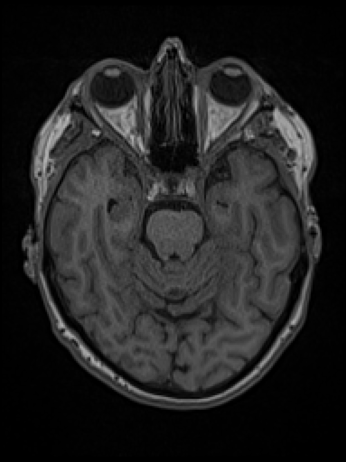

IRM T1

Test de robustesse du logiciel d'IA générative BrainGML-AD® (Société Geodaisics)

Objectif : Corréler les données de la ponction lombaire à celle de la morphométrie cérébrale issues de données IRM de patients atteints de la maladie d'Alzheimer par rapport au sujets avec plaintes subjectives et patients atteints d'autres maladies neurodégénératives.

✅ Mise à disposition d'une base de données structurée

✅ Sélection d'IRM Cérébrales

✅ Sélection de ponctions lombaires